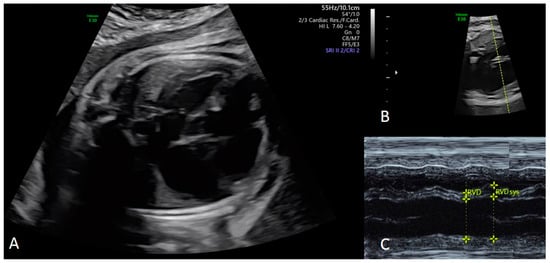

2.3. Ultrasound Assessment

4.2. Echocardiographic Evaluation